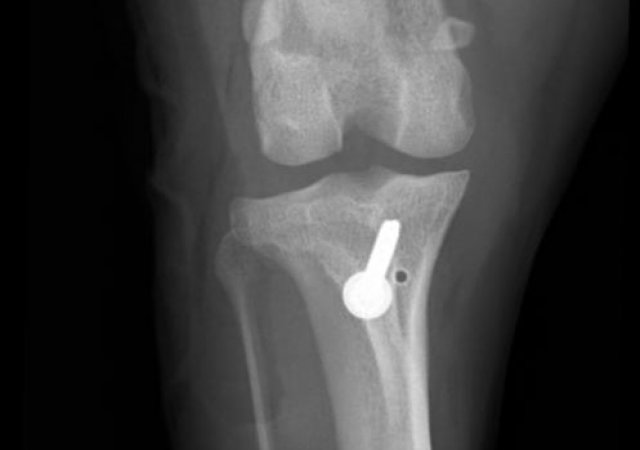

Zur Stabilisierung betroffener Knie empfehlen wir, unabhängig von der Größe des Patienten, die TPLO (Tibia Plateau Leveling Osteotomie).

Patellaluxation

Nicht nur kleine Hunde wie Jack Russel Terrier, Yorkshire Terrier, Chihuahua und co. sind von der Patellaluxation (das Herausspringen der Kniescheibe) betroffen. Die Erkrankung findet sich bei Hunden aller Gewichtsklassen und bei einer Vielzahl an Rassen wie auch Mischlingen. Auch bei Katzen treten Probleme mit der Kniescheibe auf, wenn diese nicht dort sitzt, wo sie hingehört.

Nicht in allen Fällen bedarf es einer operativen Versorgung, jedoch sollte man die mittelfristigen Folgen einer ständig luxierenden Patella auf keinen Fall unterschätzen. Es besteht das erhöhte Risiko eines Kreuzbandrisses und kommt häufig zu Abnutzungen und einer dadurch bedingten Ausdünnung des Knorpels sowie zu Arthrosen.

Unter Berücksichtigung der individuellen Faktoren jedes Patienten (u.a. Alter, Gewicht und Aktivitätsgrad) entscheiden wir, welche Therapie zu Ihrem Tier passt.

Ist eine OP unausweichlich, so wird meist eine Transposition der Tuberositas Tibiae sowie eine Sulcoplastie durchgeführt. Bestehen zusätzlich massive Fehlstellungen der Hintergliedmaßen oder eine HD, können auch weitere Operationen wie Umstellungsosteotomien oder Operationen am Hüftgelenk erforderlich werden.